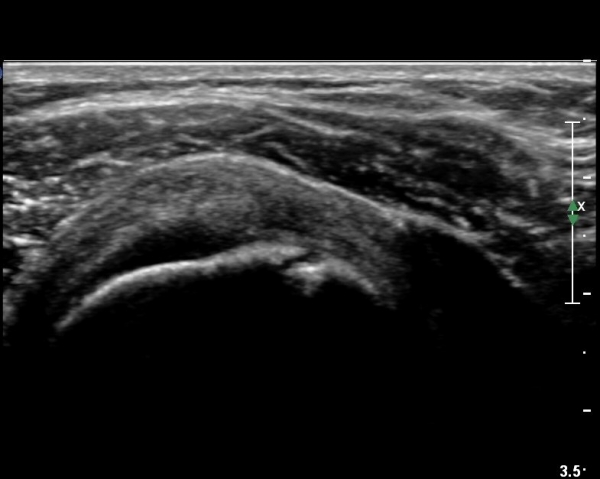

¼ºº° / ³ªÀÌ

¿©ÀÚ/ 42¼¼

ÁÖÁõ»ó

¿ìÃø ¾î±ú ÅëÁõ( ÇÑ´Þ)

º´·Â

¿Ü»ó(-). ÆÈÀ» µî±â ¾î·Æ´Ù, µÚ·Î µ¹¸®¸é ¾ÆÇÁ´Ù

ÀÌÇÐÀû °Ë»ç

°í³ªÀý°¡µ¿¹üÀ§ Á¦ÇÑ ¾ø´Ù. ¼öµ¿Àû, ´Éµ¿Àû ¿ÜÀü ½Ã ¾î±ú¿¡¼­ ÀâÀ½ÀÌ ´À²¸Áø´Ù.

ÀúÇ׿¡ ´ëÇÑ ¿ÜÀü ½Ã ÅëÁõÀÌ ÀÖ´Ù.

ÃÊÀ½ÆÄ °Ë»ç

´ë°áÀý°ú °ßºÀÇϺο¡ ¹æ»ç¼± Åõ°ú¼º °¨¼Ò(sclerosis)°¡ °üÂûµÈ´Ù(÷ºÎÆÄÀÏ).